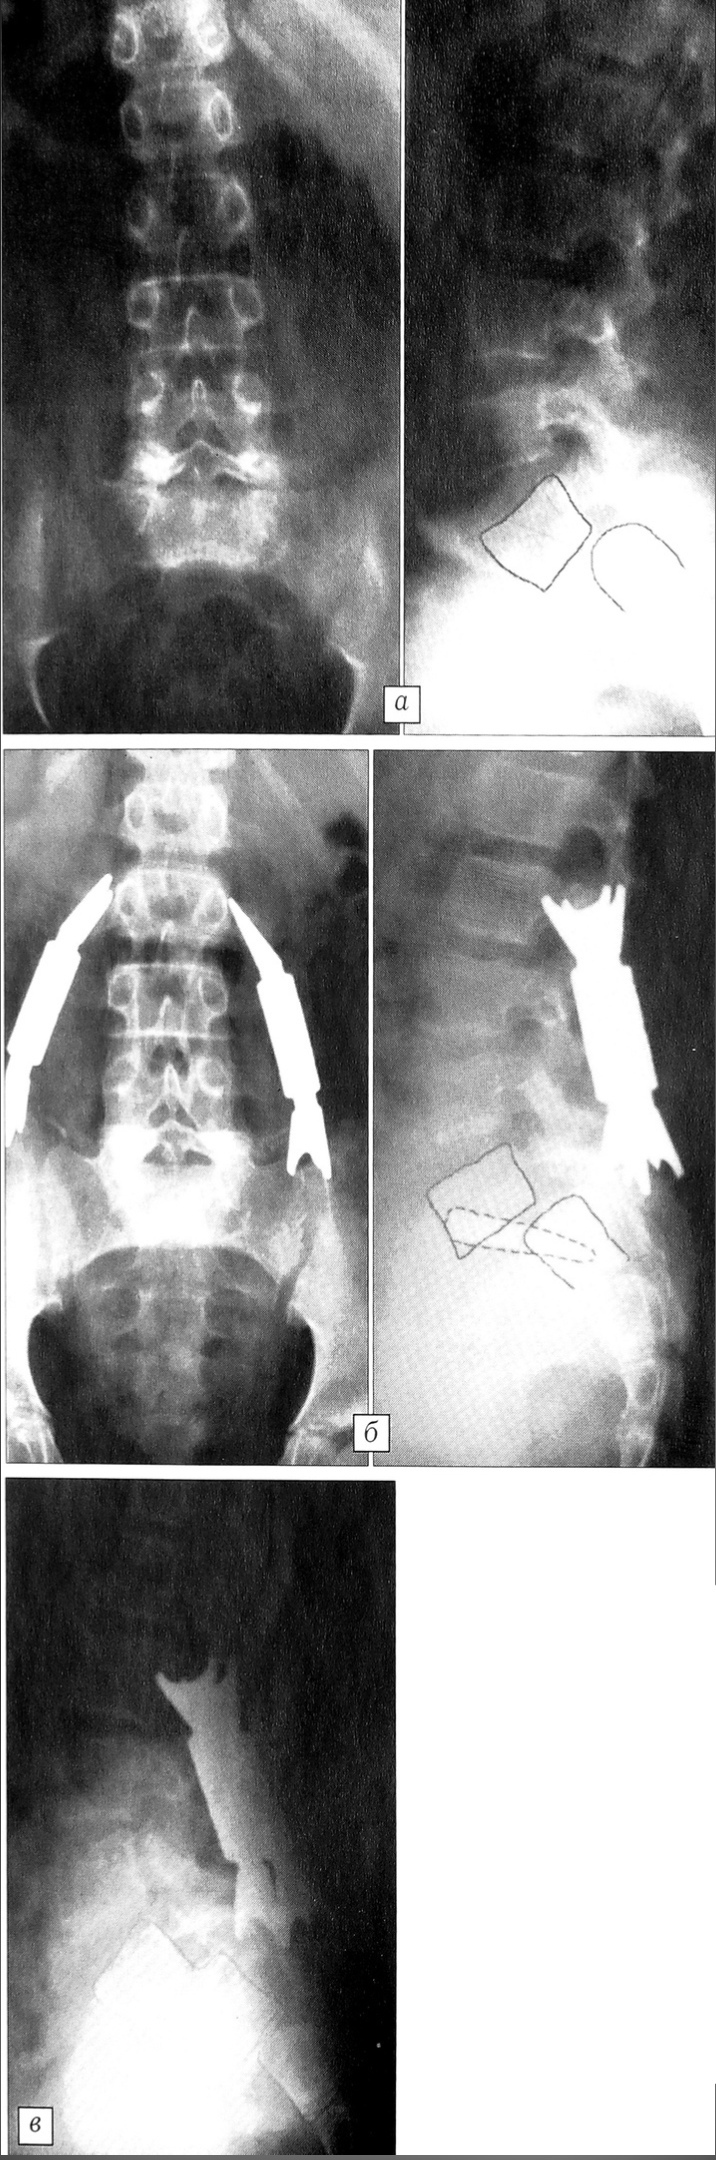

Рис. 3. Больная Л. 14 лет. Диагноз: спондилолизный спондилолистез L5 позвонка IV степени, диспластический левосторонний пояснично-крестцовый сколиоз III степени.a — миелограммы, б — компьютерная томограмма при поступлении: на КТ выраженная дисплазия дуги L5 позвонка и ее инвагинация со стенозом позвоночного канала;в — сагиттальная компьютерная реконструкция до операции, г — после операции;д — рентгенограммы после операции (ламинэктомия L5 с транспедикулярной фиксацией системой Moss-Miami, передний спондилодез).

В случае сочетания спондилолистеза со сколиозом прибегали к более протяженной фиксации. У двух больных была произведена фиксация трех позвоночных двигательных сегментов в комбинации с передним корпородезом. У одной из этих больных выраженная дисплазия задних элементов смещенного позвонка со стенозом позвоночного канала потребовала проведения ламинэктомии (рис. 3). У па

циентки с декомпенсированным грудопоясничным сколиозом III степени и спондилоптозом L5 позвонка фиксация была осуществлена от ТЗ до S1, причем транссакральные винты проведены в тело L5 позвонка. Данный вид фиксации позволил не только стабилизировать пояснично-крестцовый отдел позвоночника, но и устранить боковую девиацию туловища (перевести декомпенсированный сколиоз в компенсированный).